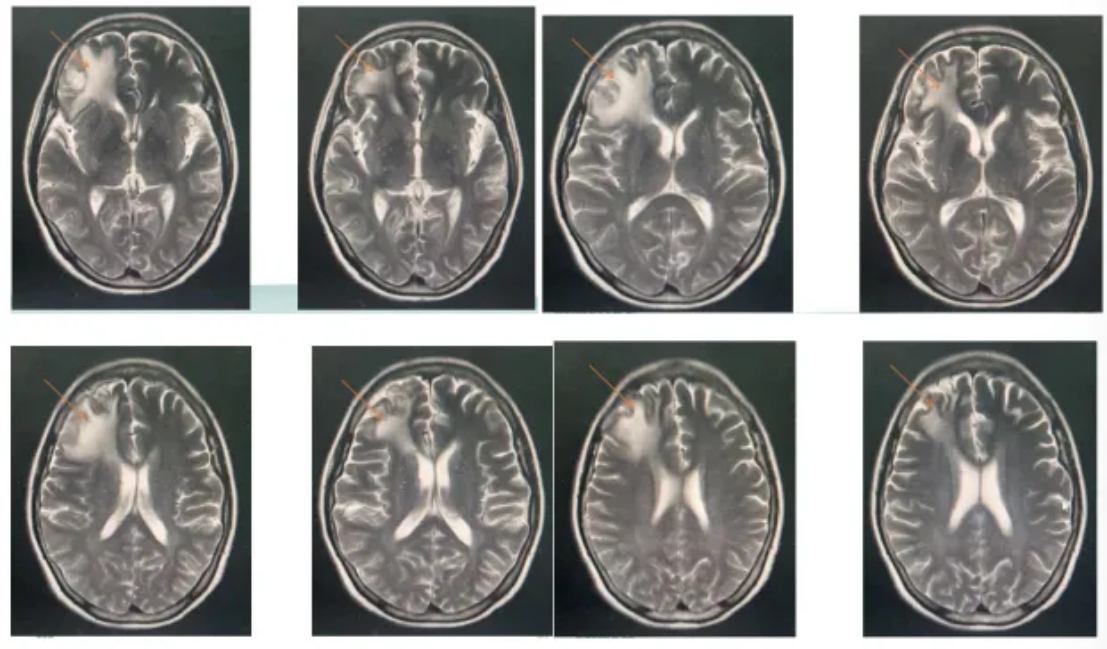

不良反应及处理:患者第一疗程结束后发生粒细胞缺乏并发热、肺炎,后面两个疗程化疗减量25%,即利妥昔单抗600mg D1,替尼泊苷100mg D2-D4,异环磷酰胺1.5g D2-D4,顺铂35mg D2-D4,地塞米松10mg D2-D4,泽布替尼160mg 2次/d,采用长效升白针预防粒细胞缺乏。

图5:影像结果

疗效评价:3疗程后达PR(图6)。

图6:影像结果